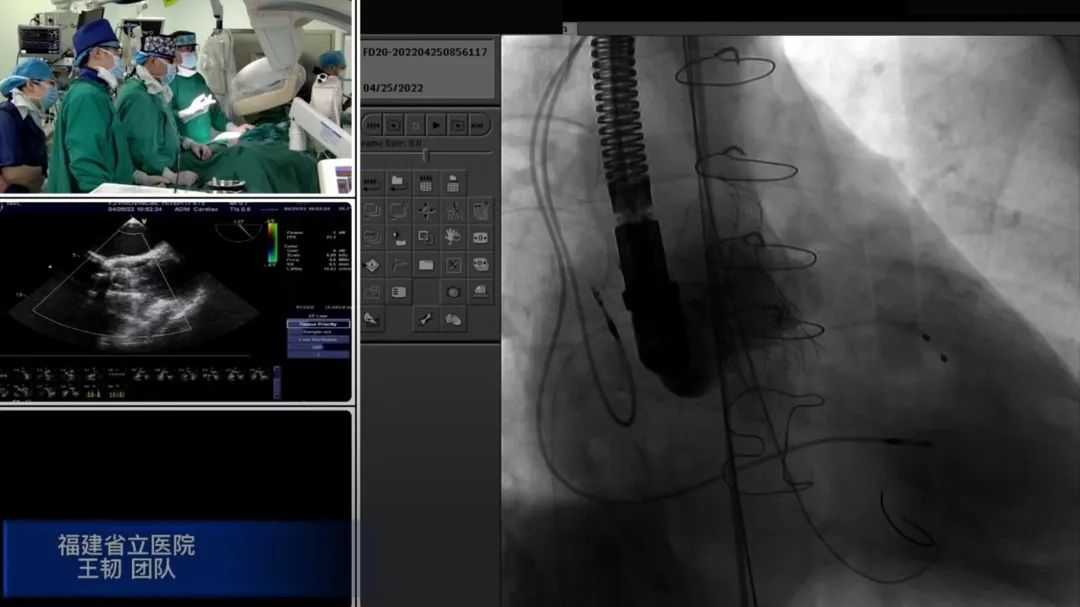

本次参赛病例为王韧团队联合麻醉二科、第二手术室、超声科(心脏超声)和重症医学四科(CCU)共同完成的1例微创主动脉瓣(TAVI)瓣中瓣植入术(VIV)。患者为72岁男性,10年前更换的生物瓣出现瓣衰,面临二次换瓣手术,因高龄、心功能差,再次外科开胸手术风险高,因此采用微创TAVI手术治疗。术中心血管外二科团队王韧主任医师、陈智群副主任医师、陈远翔主治医师、林先东医师;麻醉医师团队齐娟主任医师、方闻主任医师;护理团队陈雯护士长,陈华玲护师;体外循环阮秀璇主任医师、郑振雄主任医师;心脏超声叶振盛主治医师等密切配合,用时仅1个半小时,经股动脉为患者在衰败生物瓣中再次植入新的生物瓣膜。术后转入重症医学四科,在林风辉主任医师和林秀霞护士长带领的医护团队的精心监护下,手术当天下午拔除气管插管,术后一天即转回普通病房。心血管外二科王瑭颖护士长带领的护理团队给予患者精心护理。患者术后症状明显改善,已顺利出院。